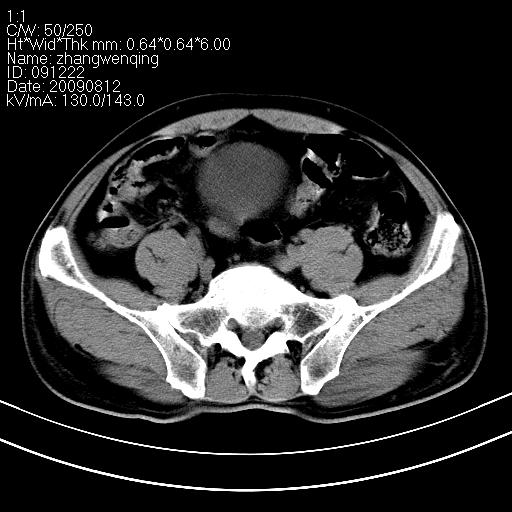

标题: CT21569:M,54Y,右侧中腹部疼痛,IVP示右侧输尿管中下段充盈缺 [打印本页]

标题: CT21569:M,54Y,右侧中腹部疼痛,IVP示右侧输尿管中下段充盈缺

右输尿管下段扩张积水。左下腹部肠管间质瘤不除外。

看不清,应打个增强,右侧输尿管扩张,右侧肠系膜上好像占位。

右侧输尿管扩张.

右侧输尿管扩张积水,考虑结石,最好做个增强除外输尿管占位性病变

右输尿管下段扩张

右侧输尿管扩张积水,最好做个增强除外输尿管占位性病变

右侧输尿管扩张积水,建议增强排除占位。

支持右侧输尿管中下段扩张积水,建议增强排除占位。

右侧输尿管下段扩张,原因待查;建议行进一步检查。

右输尿管下段扩张积水,壁增厚、边缘不光整,考虑炎性改变

ct21569:阑尾腺癌

ct21569和ct21569b(增强)结果:阑尾腺癌,侵犯回盲部及输尿管中段。手术切除部分升结肠、回肠及受侵4cm之输尿管,做回-横结吻合,输尿管支架置放术并吻合,术后病理腺癌,阑尾来源可能性大。